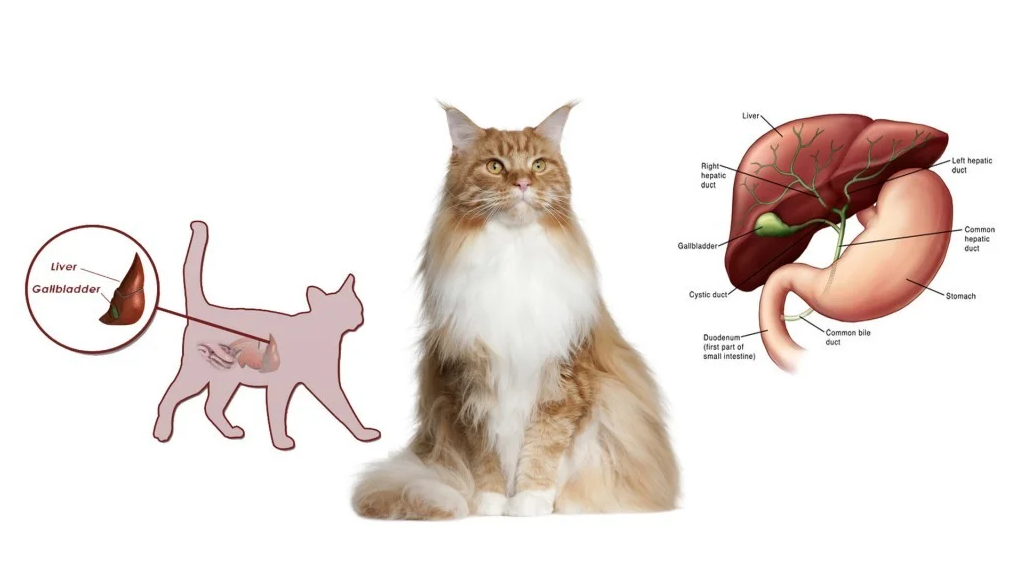

Признаки заболеваний печени: Важные симптомы и рекомендации